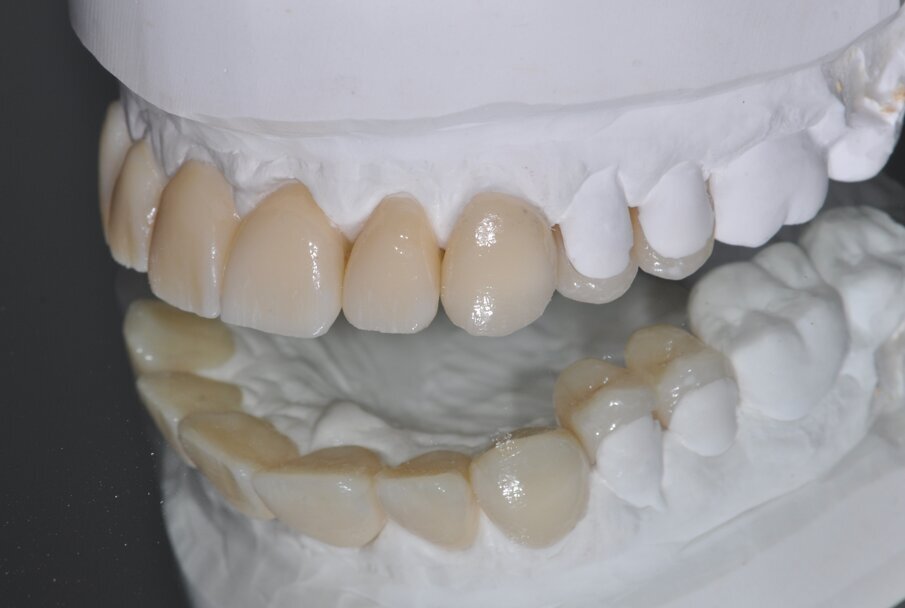

Fig. 3: Baseline situation for designing the esthetic anterior restorations following bite raising in the posterior region

In a first prosthetic treatment step, the posterior teeth were supplied with crowns (teeth 14, 26, 27, 37, and 47) and a bridge (teeth 17–15) in veneered zirconia. Teeth 32–42 were bleached and their incisal edges clinically lengthened by means of direct composite restorations (Essentia and G-Premio Bond; GC, Bad Homburg, Germany) in order to obtain a uniform esthetic result. Within the framework of the Celtra Campus Challenge, the patient could be offered a cost-effective and esthetic treatment offer upper jaw: Teeth 21 and 22 were restored with crowns and teeth 11, 12, 13, and 23 with veneers. In addition, teeth 24 and 25 received partial crowns. For the planning of the ceramic restorations, a wax-up was created and developed into a composite mock-up (Figs. 3 and 4) (Luxatemp; DMG). The tooth shade (A2) was selected based on the Vita Classic shade guide (Vita, Bad Säckingen, Germany).